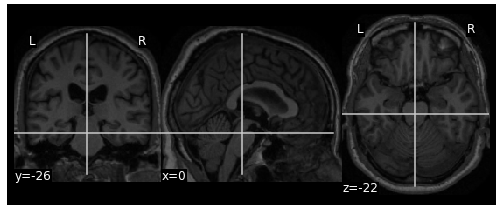

I've been trying to use the resample_to_img function to crop a T1 image based on a template. Both image are previously aligned. Every works fine using nilearn v.0.5.0:

crop_img = resample_to_img(input_img, crop_template)

plot_anat(crop_img)

produces: